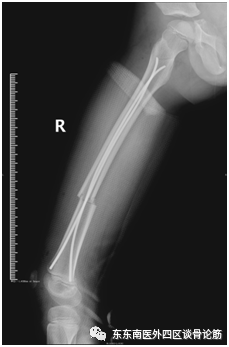

近日,我科收治了一名因房屋倒塌不慎造成右股骨干骨折的6岁男童,涛涛。

(受伤的X线片)

评估病情后,我科运用闭合复位弹性髓内针固定的微创技术对涛涛进行了手术治疗,将其断骨接上了。弹性髓内针可以做到闭合置钉,不仅可达到良好复位及良好固定的基本要求,还具有小切口微创置入,骨折处无需切开,对血供影响小,不破坏骨膜,不损伤神经,利于骨痂生长,完全符合儿童生理。这一微创治疗方式有效地降低了因手术创伤影响儿童骨折生长发育的风险。